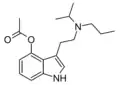

| 4-Acetoxy-MiPT | artificial | 4-OCOCH3 | CH3 | CH(CH3)2 | 4-acetoxy-N-methyl-N-isopropyltryptamine | 1024612-25-6 |